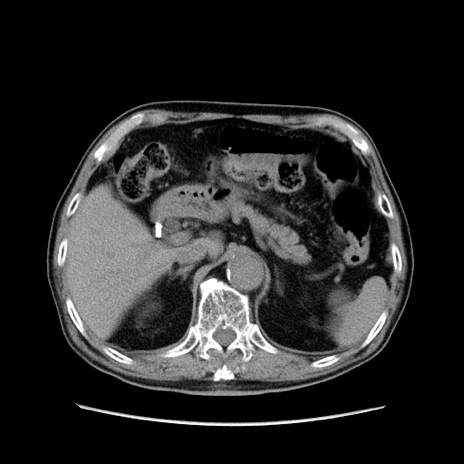

冠状断像